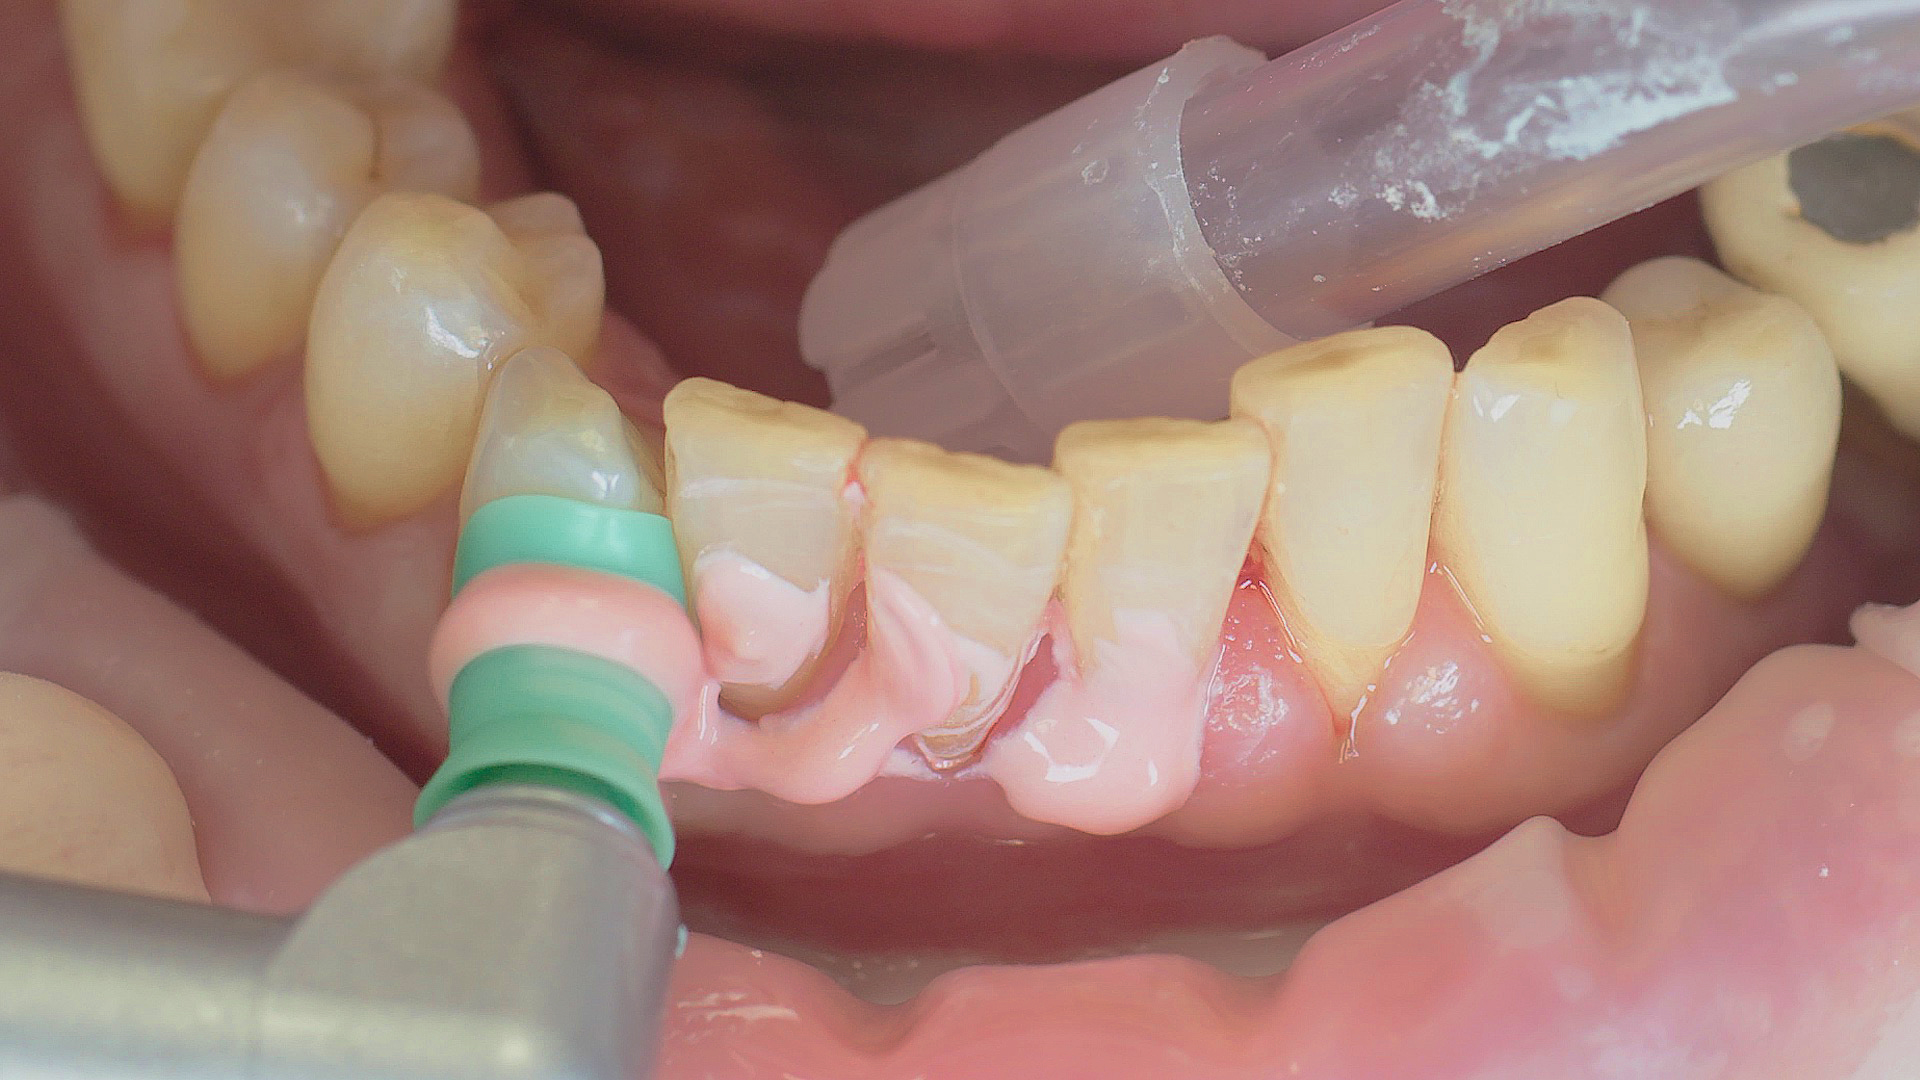

Every dental examination is based on a detailed medical history combined with targeted diagnostics con- taining as much detail as possible: The dentist records systemic risk factors such as diabetes or smoking and identifies any potential increased tendency to inflammation.[3] Hard and soft tissues are examined and periodontal pockets are probed in a screening test according to PSR (Periodontal Screening and Recording). In case of abnormal findings, the periodontal status is then re- corded and therapy is initiated where necessary. This treatment begins with professional biofilm management, by using, for example, rotary cups and polishing com pounds (Fig. 1), and comprehensive instructions in oral hygiene. Sonic or ultrasonic systems remain an effective alternative or supplement to manual instruments for sub- gingival debridement and biofilm management (presentation by Prof. Dr Ulrich Schlagenhauf; Fig. 2). Supplementary use of photodynamic therapy, air polishing or local and systemic antibiotics is not adequately documented (Prof. Dr Sema Hakki).[4] According to Dr Sergio Bizzarro, improved biomarker diagnostics may lead to an increase in customised patient therapy in the future.

Fig. 2: An air scaler efficiently performs the initial debridement, as part of initial periodontal therapy.